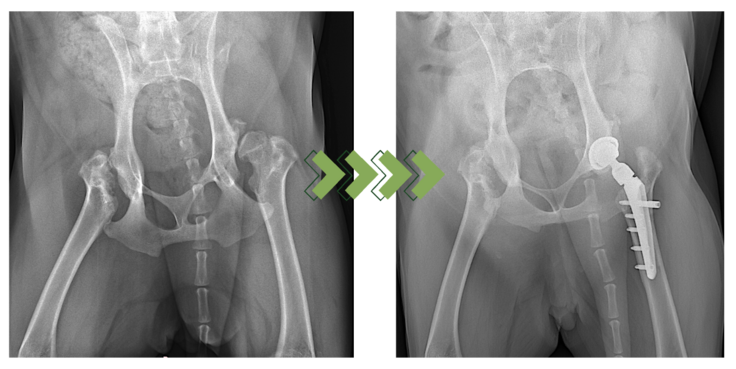

獣医整形外科学の領域において、股関節全置換術(Total Hip Replacement:THR)は、関節機能の回復が困難な股関節疾患に対する治療の一つです。

痛みの原因である変形・損傷した関節構造を人工関節に置き換えることで、正常に近い関節機能と可動性を回復し、長期的なQOL(生活の質)の向上を得ることが目的の治療法です。

股関節全置換術では、犬の体重や活動性に耐えうるように設計されたインプラントを使用する必要があります。インプラントとして大腿骨機能を置換するステム、ネック、ヘッド、 寛骨臼 機能を置換するカップで構成されており、これらを適切に設置することで股関節機能を代替することができます。